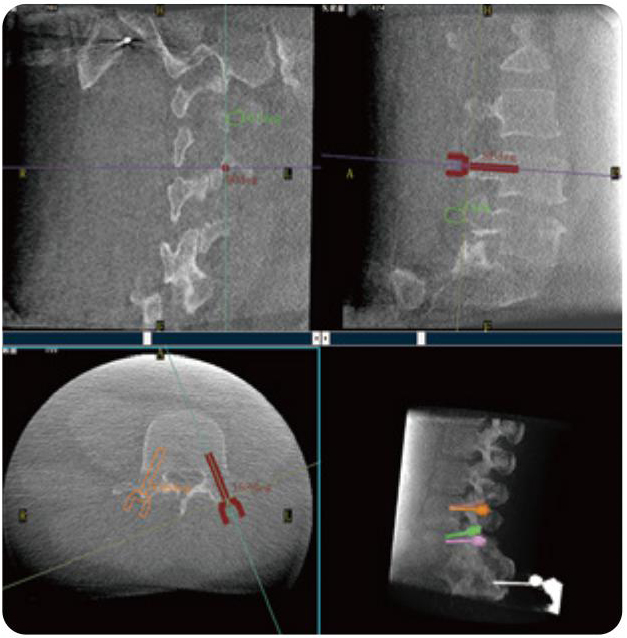

PL300B可應(yīng)用于多節(jié)段脊柱外科手術(shù),輔助醫(yī)生定位病灶部位,為脊柱外科手術(shù)(經(jīng)皮椎體成形術(shù)、椎弓根螺釘內(nèi)固定術(shù)等術(shù)式)提供術(shù)前手術(shù)流程規(guī)劃、入釘位置、角度可視化引導(dǎo),模擬仿真入釘輔助。

PL300B搭配普愛醫(yī)療自主研發(fā)生產(chǎn)的平板3D C形臂,借助一體化自適應(yīng)配準( 軌跡配準)技術(shù),通過追蹤C形臂三維采集軌跡,自動完成圖像坐標建立和系統(tǒng)坐標配準。配準精度更高,操作步驟少,系統(tǒng)運作效率高。